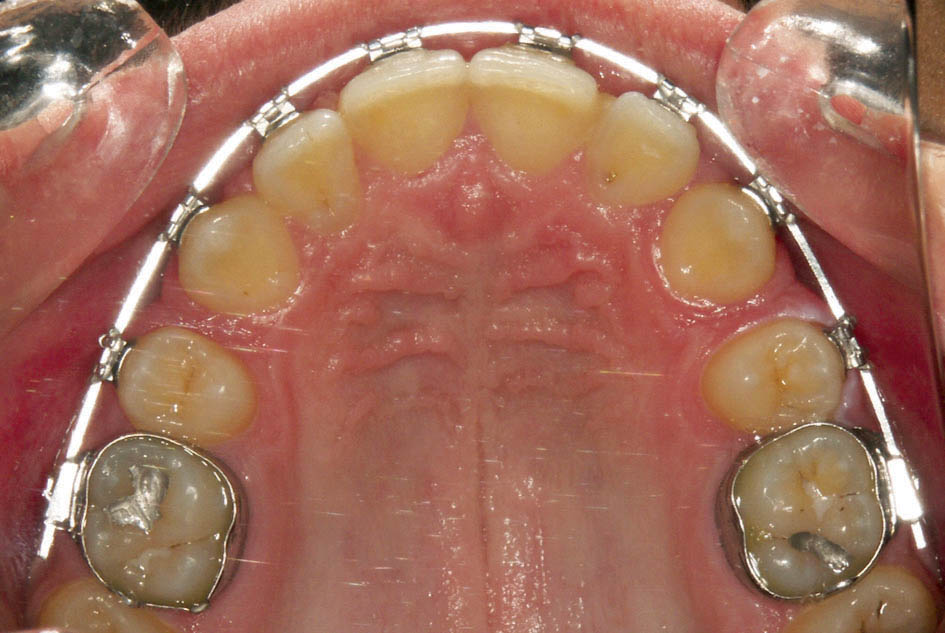

در شکل 1-3 دندانها مرتب هستند. براکت پرمولرها اشتباه چسبانده شدهاست، لذا بعد از قرار دادن سیم (شکل 2-3)، پرمولر اول که براکت آن ژنژیوالی است اکسترود و پرمولر دوم که براکت آن انسیزالی است اینترود شده و از قوس خارج گردیده است. به همین دلیل صحیح چسباندن براکتها برای مرتب شدن و هم سطح شدن دقیق دندانها بسیار مهم است.

شکل 1-3: ژنژیوالی چسباندن براکت پرمولر اول و انسیزالی چسباندن براکت پرمولر دوم